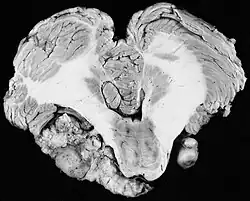

Die Erstbeschreibung der Erkrankung stammt aus den 1920er und 1930er Jahren. 1933 beschrieben W. James Gardner und Charles Frazier eine Familie, bei der sich über fünf Generationen in 38 Fällen eine Taubheit fand, die durch beidseitige Tumoren des Hörnervs verursacht waren. Zudem erblindeten 15 der beschriebenen Patienten.[1] Weitere Erkrankungsfälle wurden von Cecil Charles Worster-Drought im Jahre 1937,[2] von Anthony Feiling und Ward im Jahre 1920[3] und von Peter Moyes im Jahre 1968[4] berichtet. In der Arbeit von Worster-Drought wiesen die Autoren auf eine Beschreibung von John Henry Wishart aus dem Jahre 1822 hin. Dieser beschrieb die Erkrankung erstmals.[5] Wishart war Präsident des Royal College of Surgeons of Edinburgh. Er beschrieb einen 21 Jahre alten Mann (Michael Blair), der unter einer beidseitigen Taubheit litt. Er zeigte eine besondere Kopfform und war seit dem vierten Lebensmonat rechtsseitig erblindet. Nach dem Tod des Patienten zeigten sich bei der Autopsie Tumoren des Gehirns und der Hirnhäute. Bemerkenswerterweise beschrieb Wishart einen „Tumor von der Größe einer kleinen Nuss, der sehr hart war und beidseitig am Hörnerv zu finden war, genau an der Stelle des Meatus acusticus internus“.

Das sogenannte Akustikusneurinom bei der Neurofibromatose Typ II ist in Wirklichkeit ein Schwannom des Nervus vestibularis (Gleichgewichtsnerv). An dem falschen Begriff wird trotz besseren Wissens in der ganzen wissenschaftlichen Literatur festgehalten. Die vestibulären Schwannome wachsen langsam am inneren Eingang (Schädelbasisseite) des Meatus acusticus internus. Sie entstehen aus der Nervenscheide des oberen Abschnittes des N. vestibularis am Übergang des zentralen zum peripheren Myelin (sog. Redlich-Obersteiner-Zone) im Bereich des Porus acusticus internus, rund 1 cm entfernt vom Hirnstamm.